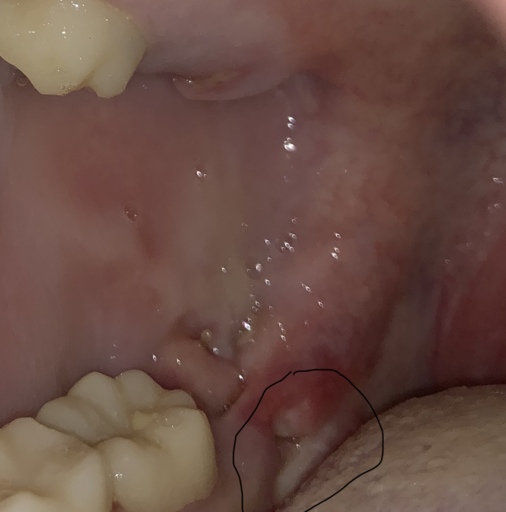

Jaw Bone Showing After Wisdom Tooth Extraction

Hello! One week ago I have two wisdom teeth removed, both being on the same side of my mouth. I had an infection on my bottom wisdom tooth and was given antibiotics prior to the extraction. Since the surgery, I have had dull pain from that one...